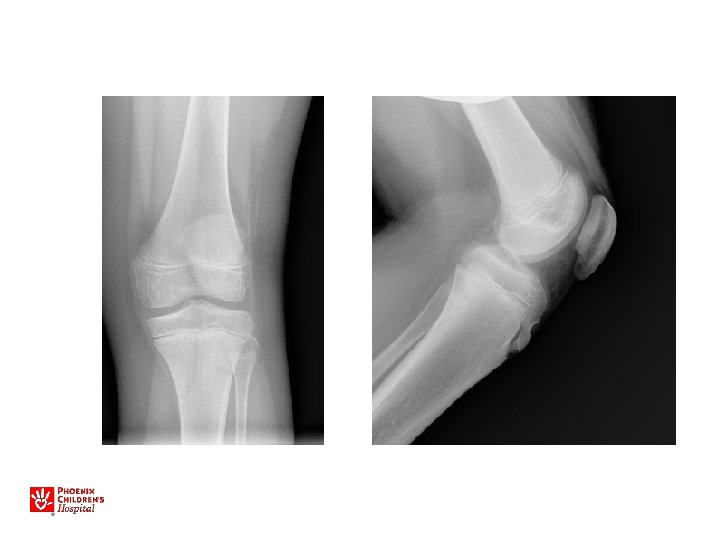

Slipped Capital Femoral Epiphysis • • 13 yo M 3 month history of left knee pain Limp at the end of the day Plays sports, has not missed practices. No history of injury. No night pain, fevers. Exam – limp, able to run, jump, no tenderness about the knee

Six Weeks Later – Referred to Peds Ortho

• • • Slipped Capital Femoral Epiphysis M>F Increased BMI Peak age around 11 -13 y. o. Walks with a limp Limited internal rotation, flexion • May walk with the foot pointed outward • Knee, Thigh, or Hip pain!

• Obtain AP and frog leg oblique x-rays • If a SCFE, make the child nonweightbearing • Send patient to ER immediately, admit to hospital for surgical fixation

12 yo F with right knee pain 3 week wait for a clinic appointment with an orthopaedist

Fell in gym class while kicking a ball Brought to ED by ambulance

11 yo M, acute unstable SCFE

SCFE: Key Points Any child with knee pain • Examine hip range of motion – Prone and supine • Check AP and frog lateral hip films, particularly if limited hip motion • Any SCFE is an urgent referral – go to ER, see orthopaedist, admit to hospital for bedrest, surgical condition